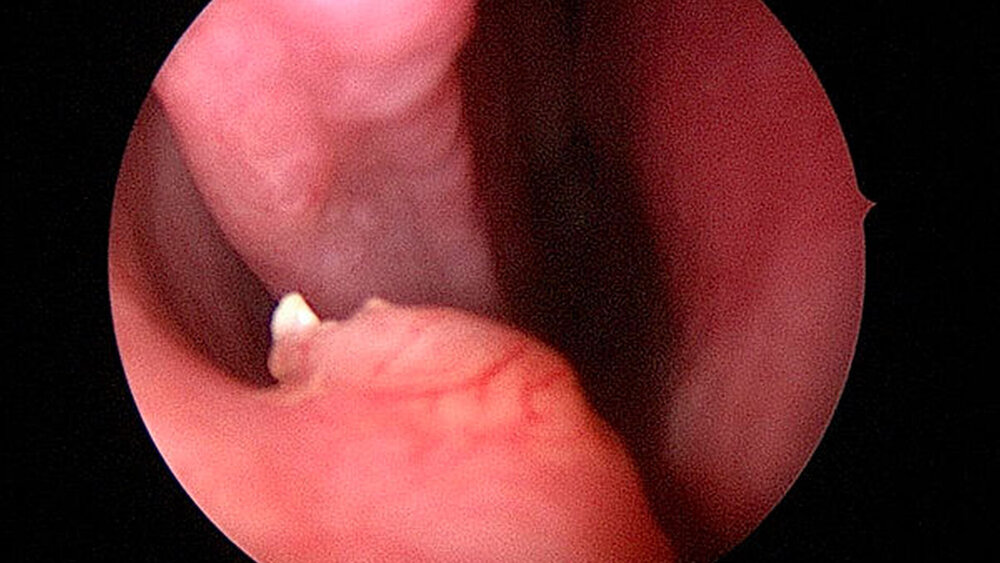

In allgemeiner Schmerzausschaltung wurde endoskopisch unterstützt eine Infundibulotomie mit nachfolgender Kieferhöhlenrevision und transnasaler Entfernung des Zahns 13a aus dem rechten Nasenboden durchgeführt (Abbildungen 3a bis 3c). Der postoperative Heilungsverlauf war komplikationslos, die definitive Histologie des entnommenen Kieferhöhleninhalts bestätigte die Verdachtsdiagnose einer chronischen Sinusitis maxillaris.